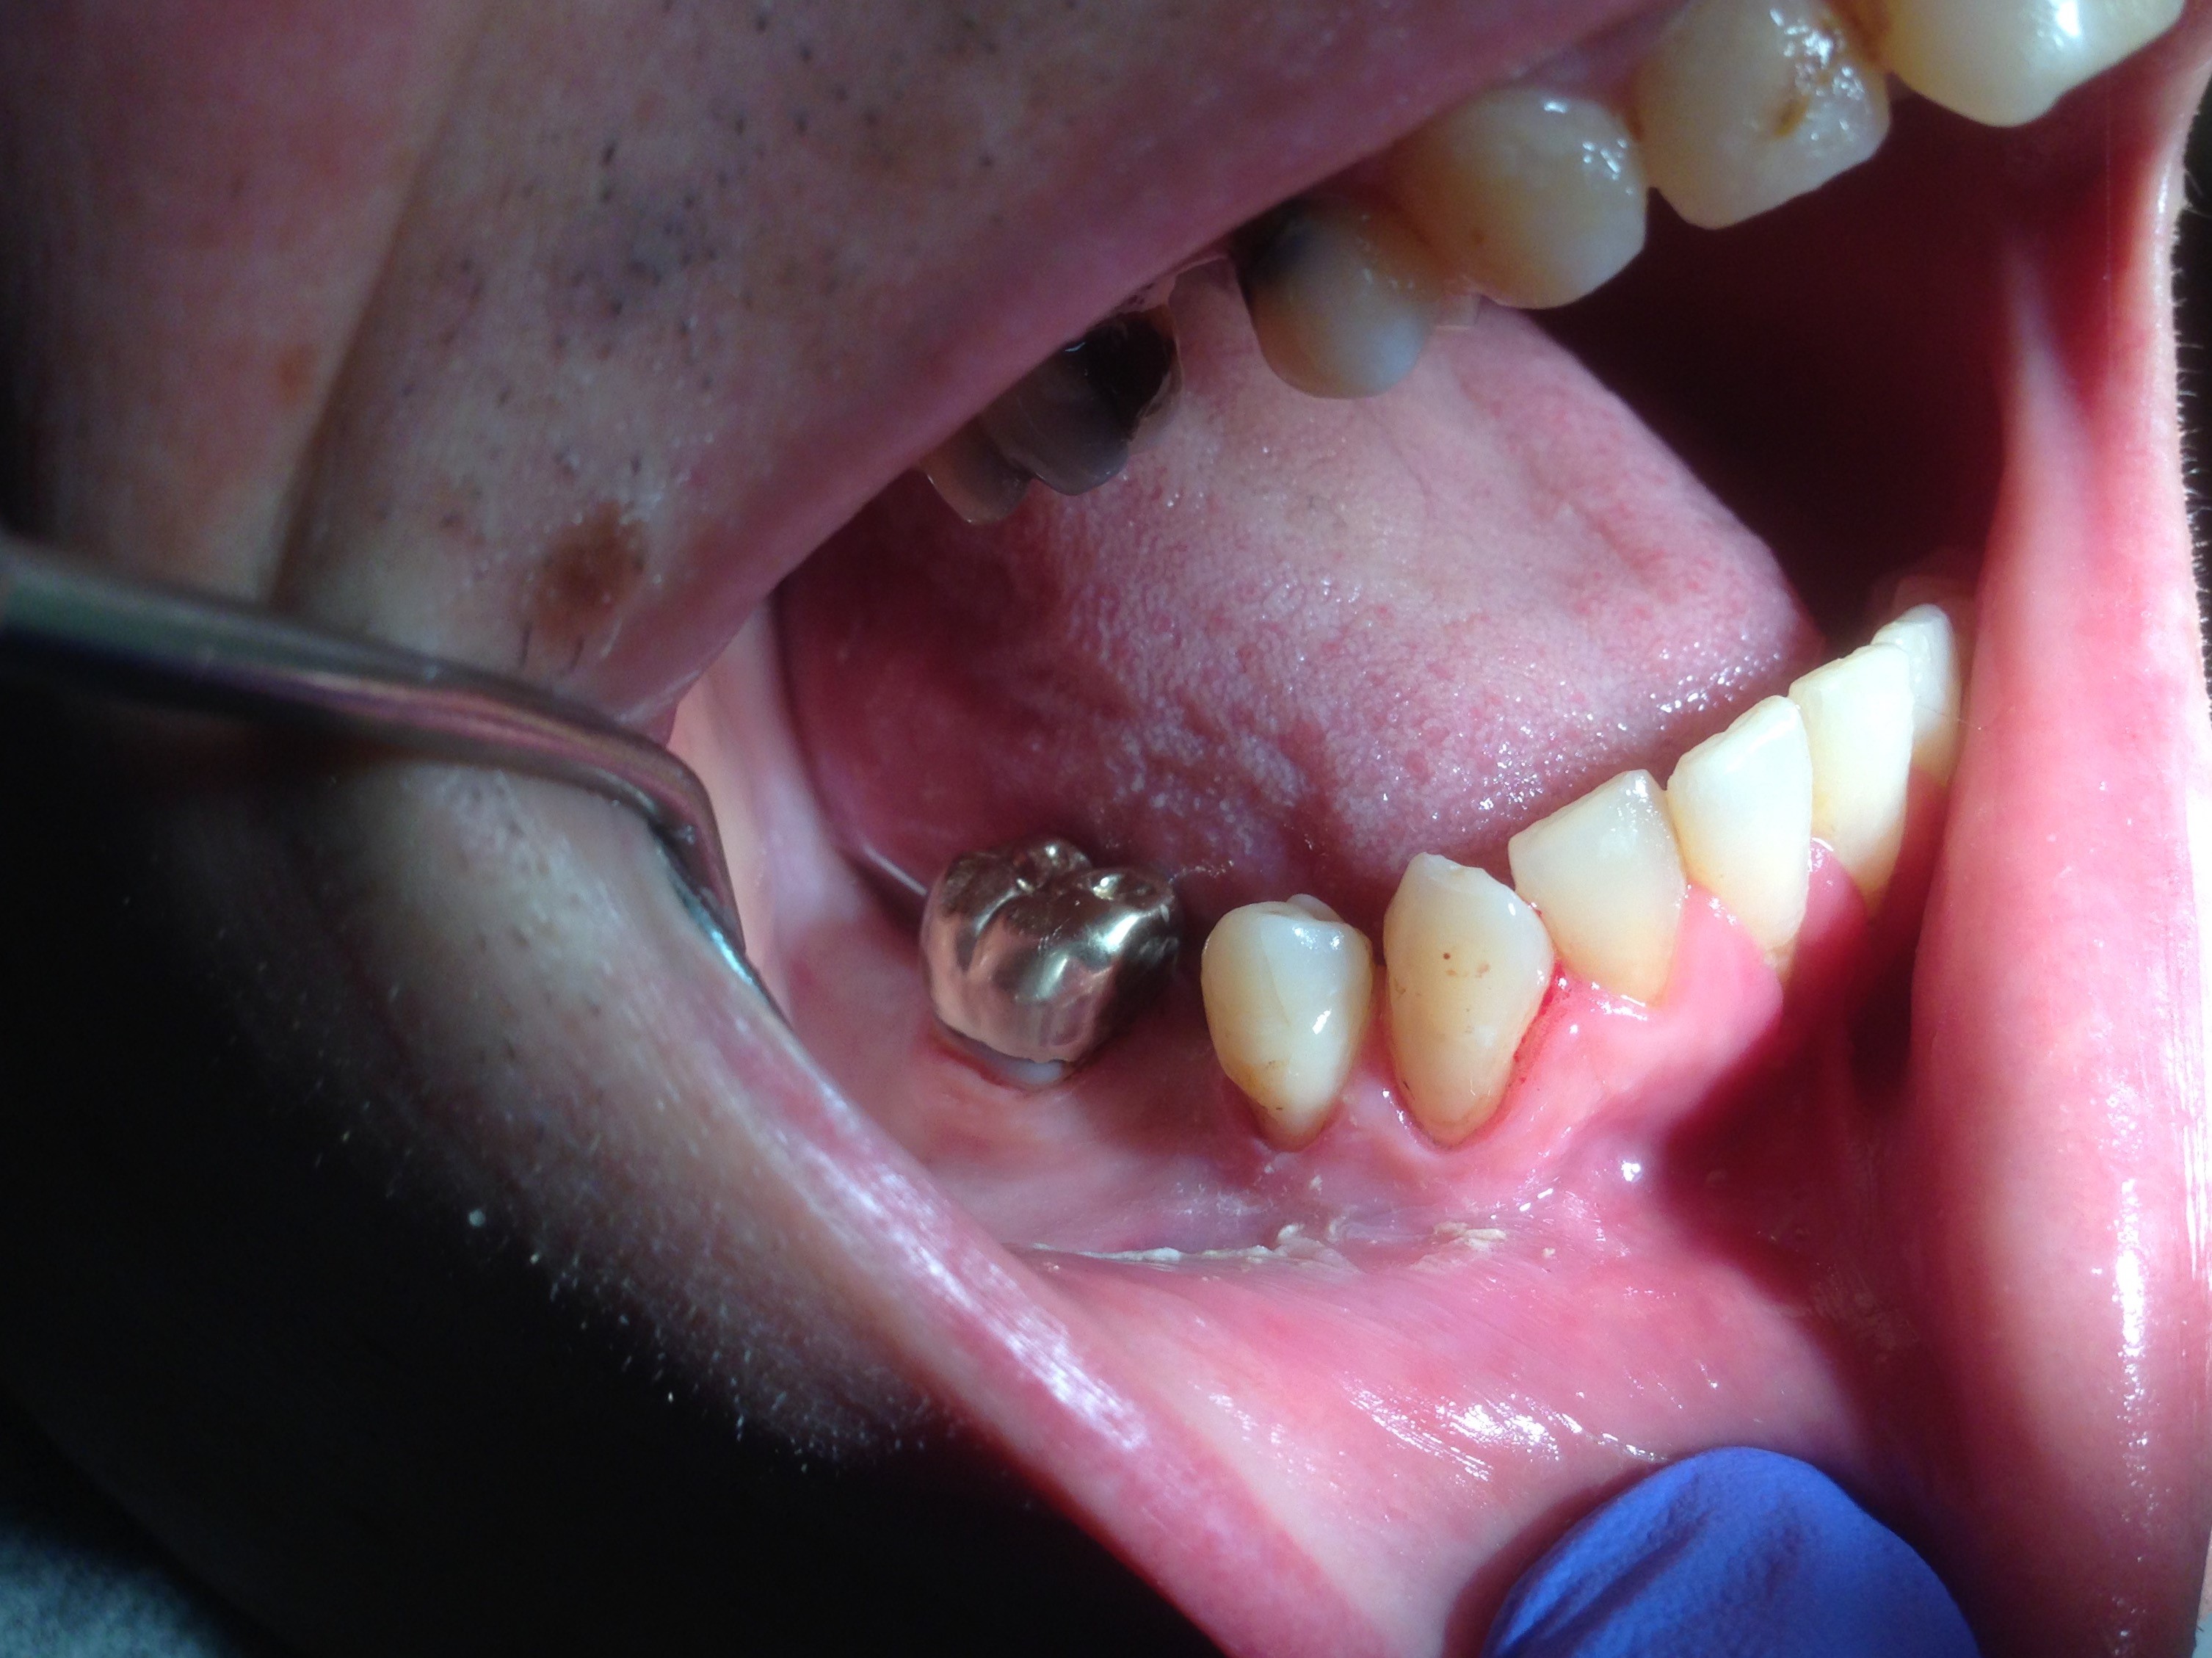

The patient shown in Figure 4 through Figure 6 was a meth user for 6 years. He had a stroke at age 22. After recovering from the stroke and stabilization of his circulatory system was achieved, and once he quit using meth, he strongly desired to apply for a job and wished to improve his dental appearance. He opted to have all of his teeth extracted, as complete dentures were his only treatment option because there were no adequate abutment teeth remaining for placement of removable partial dentures.

Fig 4 through Fig 6. Patient’s oral condition after 6 years of meth use.